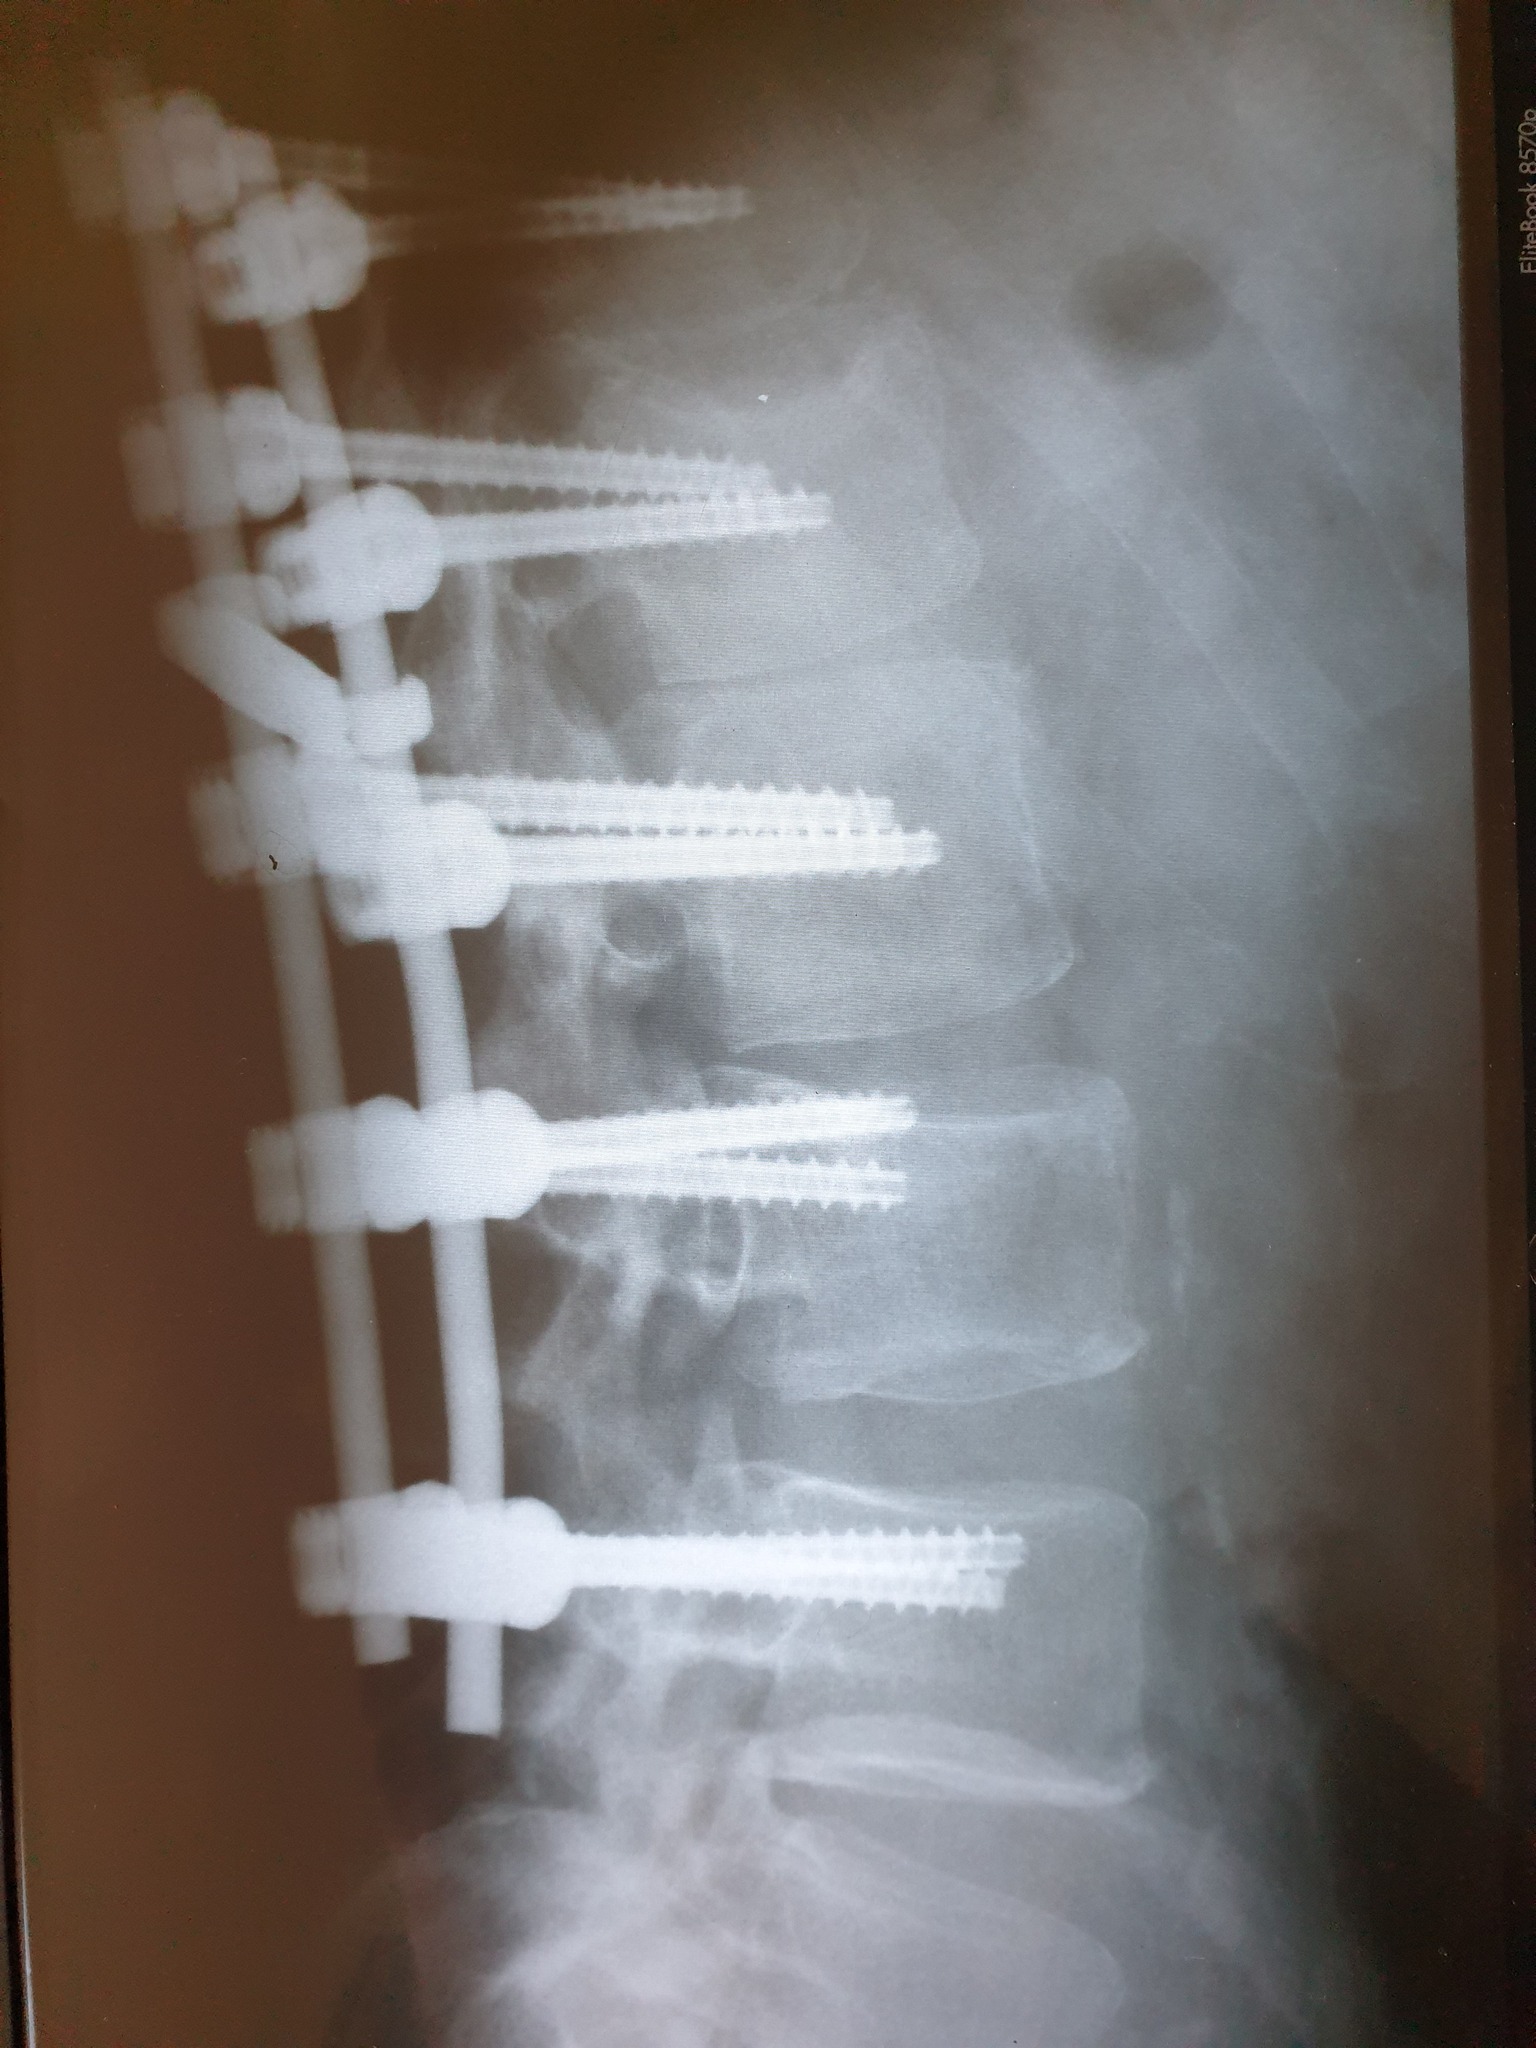

Nakon što je 11. februara doživio povredu na radnom mjestu, tačnije nakon što je pao sa lotri i slomio kičmu na dva mjesta Nino Katić je odlučio da progovori i sa svima podijeli svoje iskustvo, ali i pokaže zastrašujuće povrede koje je zadobio.

Šta dobiješ u “Centrumu” kada zbog njihovog neispravnog sredstva za rad slomiš kičmu na dva mjesta i ostaneš invalid? Pa kod neljudi dobiješ otkaz, i to poštom – rekao je Katić, a zatim je opisao šta je dovelo do teške nesreće koja se dogodila 11. februara, ali i svemu što je slijedilo nakon tog dana.

Došao je i 11. februar, taj crni 11. kada sam pao sa lotri, samo pukoše ispod mene i završio sam sa dvostrukim lomom kičme. Inspekciju nisu zvali, jedva je i Hitna pozvana, a kažu prva riječ šefova je bila: “Jeste li morali zvati Hitnu?”, Nakon toga me je zamjenica porodične doktorke oštetila svojim neradom jer mi nije htjela na vrijeme izdati uputnicu za ljekarsku komisiju na koju sam zbog toga zakasnio dva dana i uslijed čega mi je ljekarska komisija promjenila status iz “povreda na radu: DA” u “povreda na radu: NE”, znači svjesno se lagalo na zvaničnom dokumentu – objasnio je Katić za Srpskainfo.